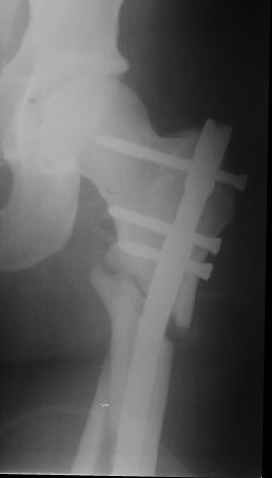

В частности, его возможности при фиксации переломов проксимального отдела бедра - в сравнении с другими, имеюшими лишь по одному статическому и динамическому отверстию и с кондуктором для введения 2 винтов.

Это было года 2,5 назад, мы тогда еще уточняли возможности шинирования с угловой стабильностью гвоздем с поперечным расположением винтов при переломах проксимального отдела бедра. Пациенту не пришлось приобретать намного более дорогой рекон или проксимальный гвоздь. В приложении еще несколько примеров применения того гвоздя при высоких переломах бедра, в том числе с более латеральной точкой входа. Гвоздь изгибаем для этого.